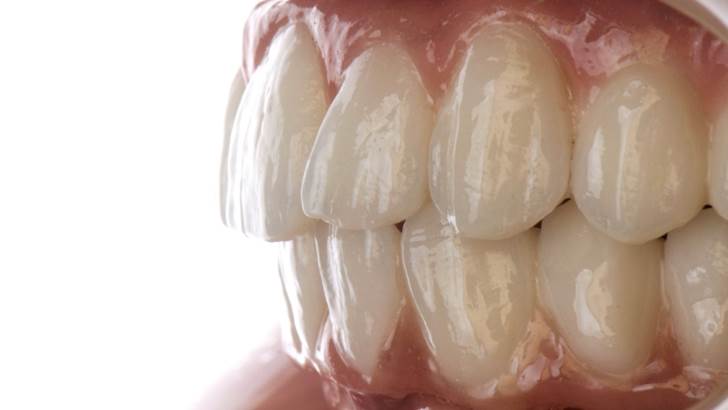

“AnyRidge shows excellent esthetic results

with Zirconia prosthesis in full-mouth rehabilitation case . ”

Clinical case: A Full transition from natural teeth to all-on-6 bridges

with AnyRidge implants